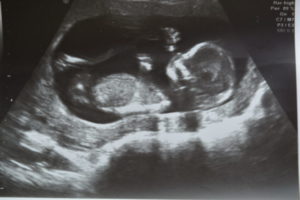

Обычно первое УЗИ врач назначает беременной к 11-12 неделе. На ранних сроках оно может поводиться при наличии неудовлетворительных анализов, болевых ощущений, кровянистых выделений. Но уже на этом сроке будущая мать желает узнать пол ребенка.

В этот период беременности диагностику могут выполнять как трансабдоминальным, так и трансвагинальным методом. Посредством вагинального датчика ультразвуковое исследование проводят из-за незначительных размеров плода. Специалисты считают, что этот метод предоставит более точные данные о состоянии эмбриона и детородных органов будущей матери.

Ультразвуковая диагностика к 11-й неделе беременности назначается не для того, чтобы определить пол ребенка, а с целью получения следующих данных:

• Точное количество ожидаемых плодов. В случае многоплодной беременности очень важно определить локализацию каждого эмбриона, а также плаценты. Беременные двойней, тройней должны находиться весь период вынашивания малышей под пристальным наблюдением акушера-гинеколога;

• Уточнение правильного расположения эмбриона в матке. Только таким образом можно исключить внематочную беременность;

• В зависимости от размеров эмбриона специалисты устанавливают срок беременности, а также рассчитывают предположительную дату родов;

• В 11 недель УЗИ может показать наличие хромосомных патологий у малыша;

• На этом сроке отлично прослушиваются сокращения детского сердечка;

• Специалист определяет правильность формирования, деятельности всех органов ребенка;

• Обнаружение возможных патологических изменений в течение беременности, например, повышение тонуса матки, отслаивание плаценты.

УЗИ на 11 неделе считается очень важной процедурой. Нельзя от нее отказываться и пренебрегать ею. На этом сроке будущая мать может получить первое фото будущего ребенка благодаря 3d, а также 4d диагностике. А вот пол малыша останется пока еще загадкой.

Пол плода уже сформирован, но определить его на УЗИ еще достаточно трудно.

На 11 неделе вынашивания плода специалисты измеряют следующие показатели:

• У женщины измеряют размер матки. Он может быть 10,5 – 12 см;

• Копчико-теменной размер. Он заключается в измерении длины плода начиная от его головы и заканчивая копчиком. КРТ в норме составляет 35 – 55 мм;

• Определение толщины воротникового пространства. Воротниковое пространство представлено складкой с жидкостью внутри. Она расположена на задней поверхности шеи плода. В норме воротниковое пространство должно быть до 2 мм. Если оно утолщено, тогда у специалистов возникают подозрения на развитие хромосомных отклонений (синдром Дауна);

• Частота биений сердца. К этому сроку нормой ЧСС считается 140 – 169 ударов/минуту;

• Рост плода – около 55 – 57 см;

• Вес – около 12 гр.;

• Длина бедра – в пределах 8 мм;

• Бипариетальный размер головы – в пределах 19 мм;

• Обхват груди – 19 – 20 мм.